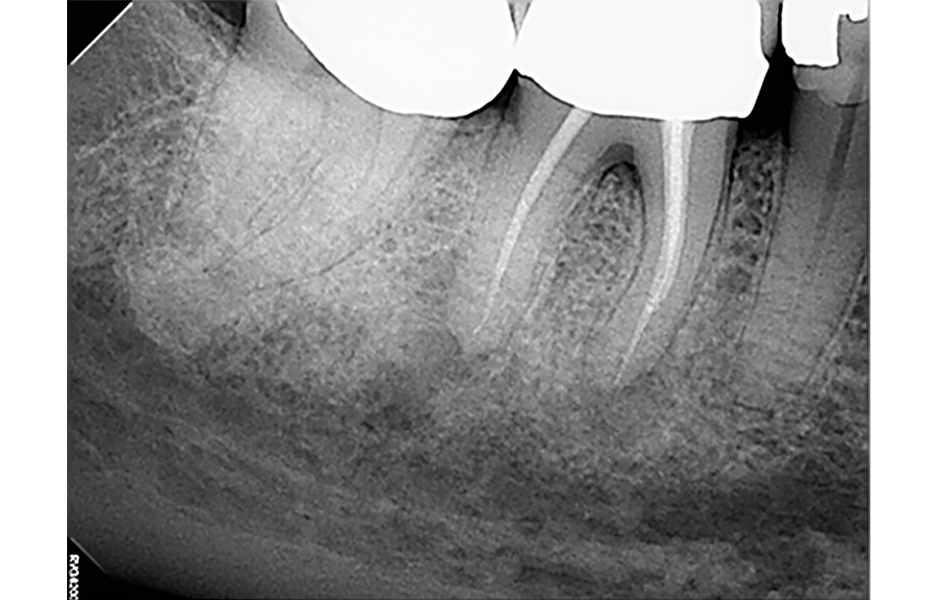

Pro radiologickou diagnostiku byl pořízen periapikální (PA) rentgenový snímek (obr. 1) a CBCT snímek s omezeným zorným polem (obr. 2a–d). Předchozí endodontické ošetření zahrnovalo zaplnění tří kanálků s nedostatečnou hustotou výplně v apikální třetině meziálních a distálních kořenů. V oblasti apexů meziálních (3 × 3 mm) a distálních (3 × 5 mm) kořenů byla patrná periapikální projasnění. CBCT (obr. 2a–d) potvrdilo nezaplněný distolingvální (DL) kanálek a možný střední meziální (MM) kanálek; koronální CBCT řez meziálního kořene (obr. 2c) také naznačuje přítomnost apikální delty spíše než jediného apikálního foramenu. Nebyly zjištěny žádné známky prasklin či fraktur.

Obr. 2a, b: Předoperační CBCT řezy zubu 46 – a) sagitální, b) axiální.

Obr. 2c, d: Předoperační CBCT řezy zubu 46 – c) meziální kořen, d) distální kořen.